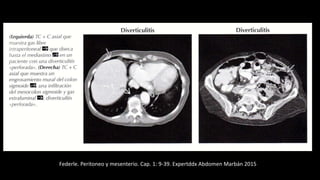

Hemoperitoneo

Federle. Peritoneo y mesenterio. Cap. 1: 9-39. Expertddx Abdomen Marbán 2015

Indicios útiles para diagnósticos

frecuentes de hemoperitoneo